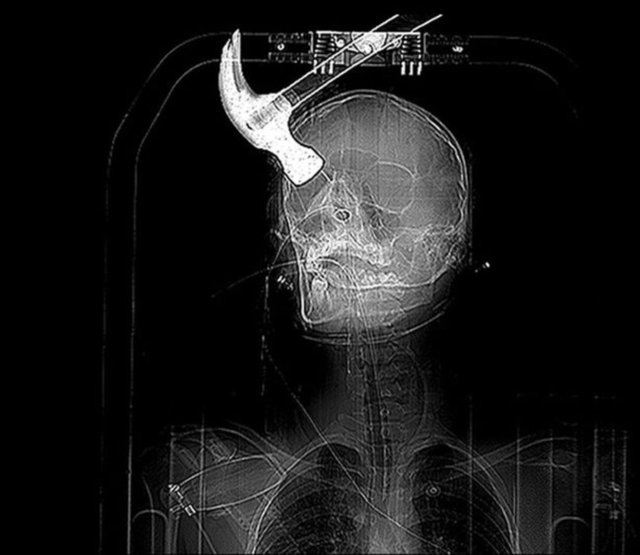

21 yaşındaki Joseph Williams ev arkadaşı Connor Huntley onu kızdırınca başına çekiçle vurdu.

Fotoğrafta gördüğünüz adam başına gelenin şokuyla bu fotoğrafları çekti, internette rekor kırdı. Çünkü hayatta kalması bir mucize.